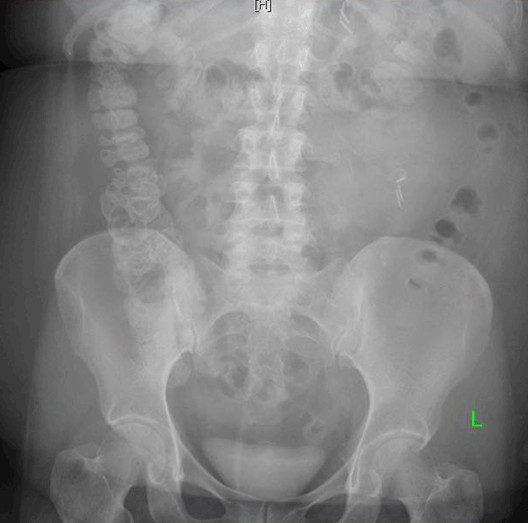

A 50-year-old female presented with a past medical history of gastroesophageal reflux, hypertension, hypothyroidism, inflammatory polyarthropathy, and obesity with a BMI of 44 kg/m2. Her surgical history included tonsillectomy, hysterectomy, cholecystectomy, and left knee replacement. Her medications included omeprazole, plaquenil, levothyroxine, and liothyronine. The patient underwent laparoscopic Roux-en-Y gastric bypass and hiatal hernia repair. She tolerated the procedure well, was functioning within normal limits, and was subsequently discharged on postoperative day-1. The patient was doing well on her follow-up appointment on postoperative day-5 where she was tolerating 80 oz of fluid a day; well above the minimum requirement. However, a few hours later the patient developed severe cramping epigastric pain, nausea, vomiting, and presented to the emergency department. The patient had a CT scan of her abdomen and pelvis, which showed obstruction at the level of jejunojejunostomy. There was no evidence of a leak or abscess (Figure 2). After intravenous fluid resuscitation, an X-ray of the abdomen and pelvis was performed eight hours later and showed transit of contrast into the ascending and transverse colon (Figure 3). However, given the lack of resolution of her symptoms, she was taken to the operating room urgently. A diagnostic laparoscopy was performed revealing a single adhesion of her jejunojejunostomy down to the base of the mesentery, effectively torsing the distal Roux limb. An adhesiolysis was performed. The patient recovered well, tolerated fluids, and was discharged one day later. However, at her follow-up appointment 12 days post Roux-en-Y and six days post adhesiolysis, the patient again developed nausea, vomiting, epigastric pain and dysphagia. She denied fevers, was not tachycardic, and had no signs or symptoms suggestive of infection. An outpatient Gastrografin swallow test was performed. The films were interpreted as showing no evidence of anastomotic obstruction or leak. However, it was suggestive of significant narrowing of the gastrojejunal anastomosis site and marked distal esophageal dysmotility as there was a five-minute delay of transit from the distal esophagus into the gastric pouch (Figure 4). Due to her persistent symptoms and impaired oral intake, the patient was directly admitted to the hospital.

Figure 3: Abdominal and pelvic X-ray showing contrast from recent computed tomography scan has progressed through the small bowel and is now present in the right colon and transverse colon. Taken on postoperative day-6.